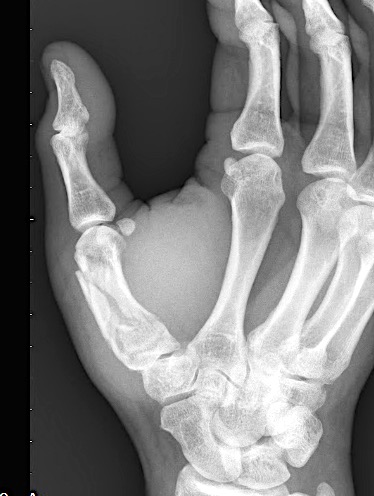

Case 1:

A 64-year-old male suffered a multi-fragmentary fracture of his right thumb metacarpal (Fig 1). An adapted 12-hole strut plate from the variable angle locking hand system was the implant of choice for fixation (Figs 2 - 4).

The strut plate provided good stability in a comminuted extraaricular fracture pattern and enables immediate mobilization. Bone callus formation was not witnessed during the healing process.